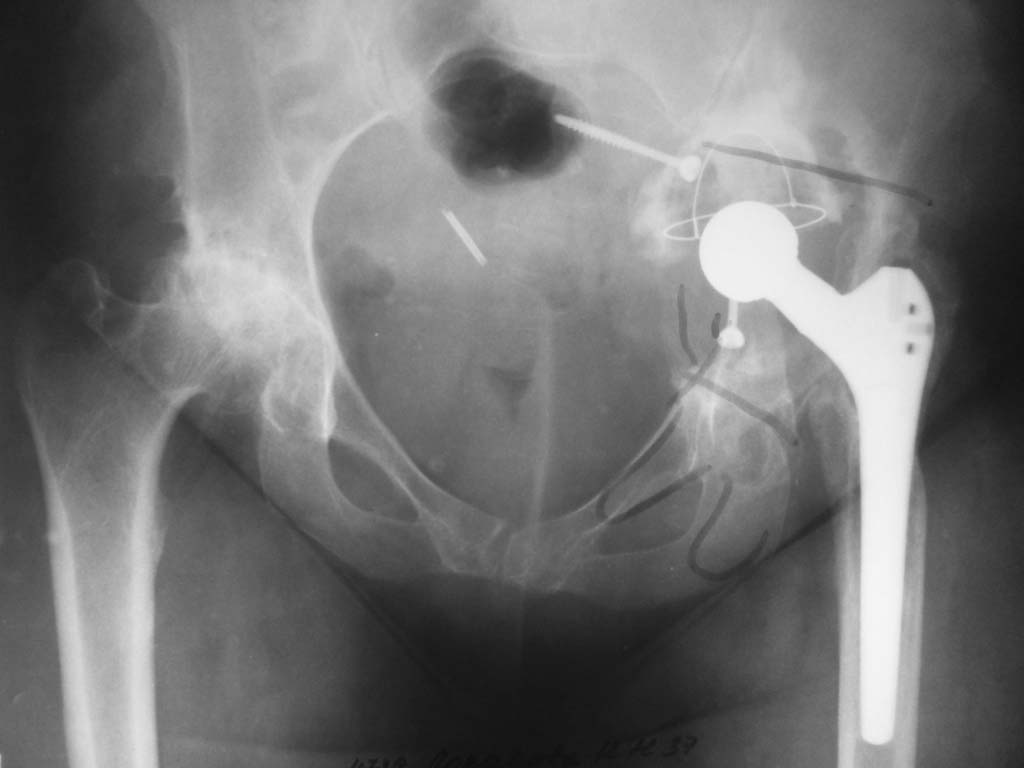

Здравствуйте коллеги! В 2006 г. была оперирована молодая пациентка: Дисплазия, коксартроз

(фото 1). Выполнели аутопластику крыши вертлужной впадины, использовав резецированную

часть бедра, гибридное эндопротезирование WL BetaCone (фото 2,3). В течение, почти 6 лет,

больная была счастлива. В 2012 г пришла при помощи костылей, с катастрофической картиной

(фото 4). Беспокоят боли, нарушение функции и пр. Местно:небольшой отёк, гиперпигментация

по наружной поверхости бедра, в крови высокое СОЭ, температура N. На УЗИ и пункционно - пока

ничего нет. Наши технические возможности не позволяют выполнить ревизионное

эндопротезирование,т.к. часть таза лизирована. Направил на консультацию в два НИИТО.

Специалисты согласны, что надо делать ревизию (в два этапа), но в тоже время отсылают больную

обратно: "иди туда где делали". Предложил пациентке убрать эндопротез. Отказ,

мотивированный тем, а что я буду делать дальше?

Как можно помочь? Для неё имеется квота.

Думаю, что необходимо выполнять эндопротезирование тазового компонента индивидуальным

имплантом.Какие будут Ваши предложения коллеги?